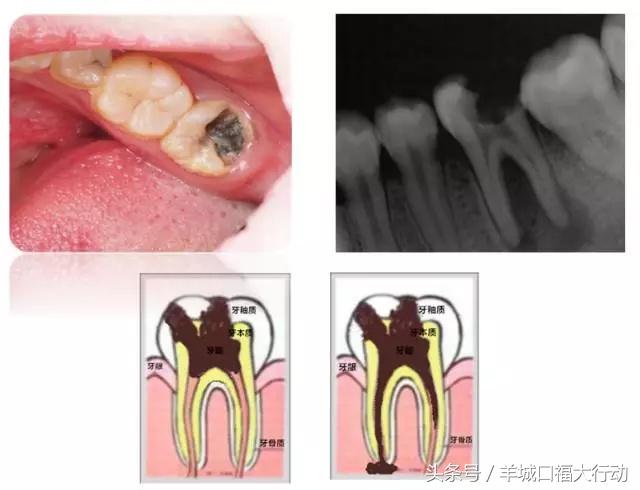

我们的牙齿跟木头一样,年久失修不注意保养就会蛀掉。看下面的牙齿,黑色和黄色的部分就是蛀坏的部分。

龋齿的形成是一个相对较缓慢的过程。根据龋齿的深度,我们分为三个不同的阶段,浅龋、中龋和深龋。不同的阶段有不同的症状。

当牙釉质持续的破坏腐蚀后,就会慢慢形成浅表的破坏。浅龋可能是黑色的窝沟或者很小的龋洞,也可以仅仅表现为白色的斑块。这个时候因为牙齿破坏小并且没有明显的症状往往很难引起人们的注意。然后龋洞逐渐扩大,进入到牙本质形成较大的龋洞,这时食物会卡在洞里面,有可能吃点甜食就会酸痛。再往下发展达到牙本质深层形成深龋时,症状就更明显了,冷热刺激时都会感到疼痛。像图中这颗牙破坏的范围很广,整个牙齿表面都变黑了。

深龋再往下发展会变成什么呢?当龋坏累及到牙神经,就会引发牙神经发炎和牙根发炎,我们称之为牙髓炎和根尖周炎。这时候疼痛会更剧烈,情况就比较严重了,治疗手段也会变得更复杂。所以说“小洞不补,大洞吃苦”,一发现龋齿就要去医院检查。